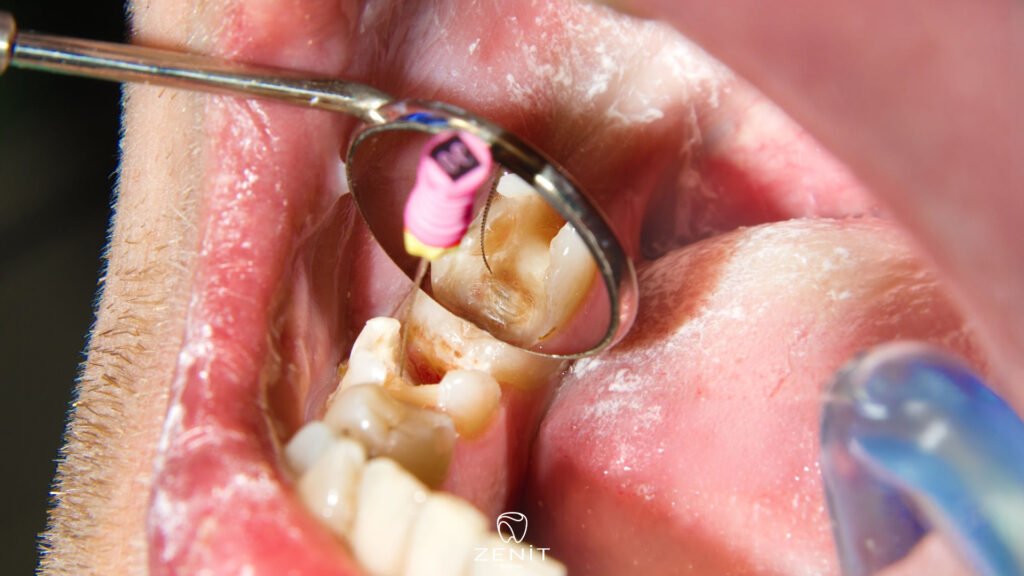

Retreatment, yani dişin yeniden tedavisi, aslında önceden yapılmış kanal tedavisinin bir “gözden geçirilmesi” gibi düşünülebilir. İşlem başladığında, diş hekimi ilk olarak eski dolgu veya tıkaç malzemeleri dikkatlice çıkarır. Bu adım, dişi yeniden temizleyip enfeksiyonu tamamen ortadan kaldırmaya hazırlamak için oldukça önemlidir. Eski dolgunun çıkarılması sırasında diş, tekrar şekillendirilmeye ve tedaviye hazır hale getirilir.

Sonrasında, dişin içindeki kanallar titizlikle temizlenir. Buradaki amaç, eski tedaviden kalan enfekte dokuların tamamen yok edilmesidir. Bazen enfeksiyon gözle görülmeyebilir ama dişin içinde sessizce ilerleyebilir. İşte bu yüzden kanalın derinlemesine temizlenmesi, retreatment’in en kritik aşamasıdır.